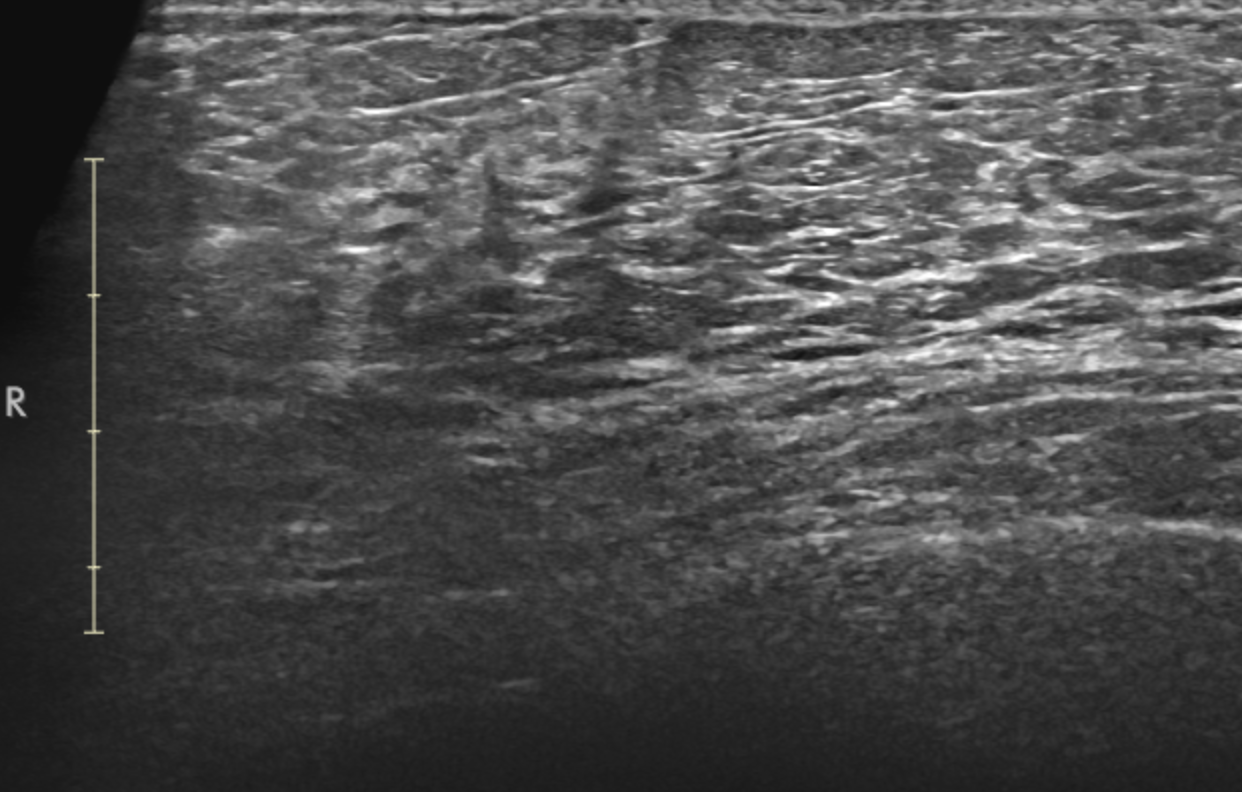

Handheld Breast ultrasound

2D Ultrasound is a traditional imaging method that uses high-frequency sound waves to create flat, two-dimensional images of breast tissue. It’s commonly used for evaluating specific areas of concern, such as palpable lumps or abnormalities detected in mammograms. Handheld ultrasounds are operator-dependent and require a skilled technician to obtain accurate images which are then interpreted by a radiologist. It may involve compression, which can cause slight discomfort for some patients. This test is FDA-approved and widely available. Currently women are told they MUST have a mammogram in order to have an ultrasound, patients find it difficult to opt out of the mammogram. No one should ever feel pressured, intimidated, bullied or shamed for choosing NOT to have a mammogram.

HerScan utilizes standard handheld breast ultrasound technology for its mobile breast screening services and does not need a doctor’s referral.